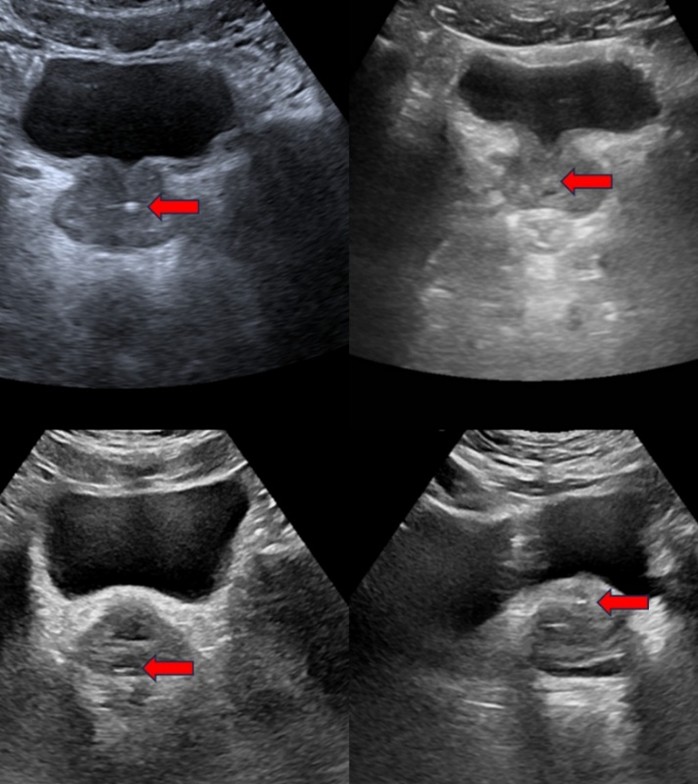

图1:超声影像中不同类型前列腺钙化的表现(箭头处)